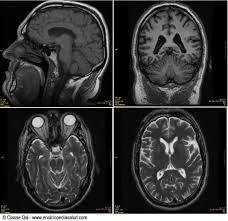

2. Resonancia magnética nuclear

1. Esta técnica es ideal para la detección de tumores muy pequeños, que pueden resultar invisibles para la técnica tradicional por rayos X. La RMN está basada en las alteraciones magnéticas que sufren las moléculas de agua en el organismo.